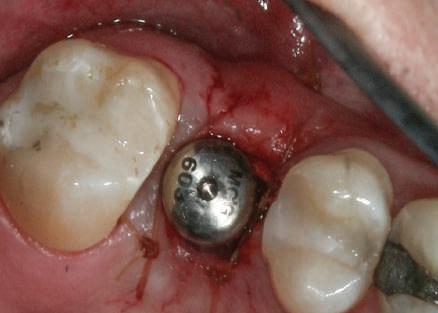

Cazul (4)

Bonturi provizorii

Acest pacient s-a prezentat cu dentiţia mandibulară laterală dreaptă eşuată din cauza unei fracturi radiculare verticale şi a cariei secundare. Autorii au utilizat cilindri de bonturi provizorii, cu şurub, ca metodă iniţială de retenţie pentru puntea provizorie după prima etapă de tratament, care a inclus extracţii şi inserarea de implanturi. Atitudine: Cilindrii temporari înşurubaţi pe implanturi după inserare sunt prezentaţi în fig 13. Ei au fost cimentaţi la carcasa acrilică prefabricată construită pe baza wax-up-ului diagnostic al pacientului (fig. 14). După îndepărtarea acrilatului excesiv, s-a

inserat proteza provizorie fixată cu şurub (fig. 15).

Cazul (4): Bonturi provizorii

Figurile

13. Cilindrii temporari înşurubaţi pe implanturi.

14. Cilindrii cimentaţi la o carcasă prefabricată din acrilat.

15. Proteza fixă provizorie fixată cu şuruburi.